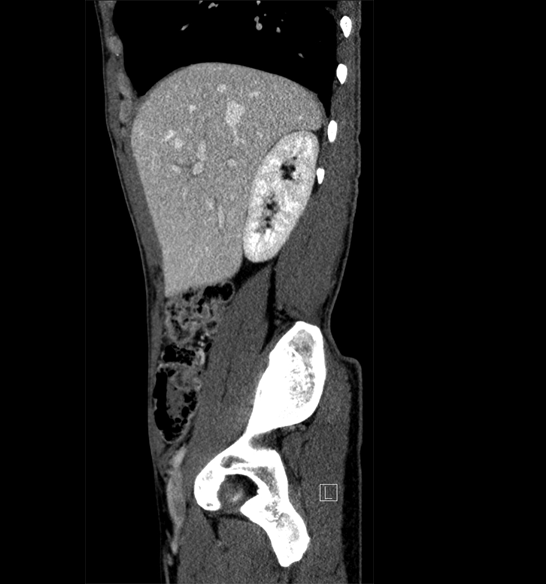

Body

Covers abdominal CT anatomy.